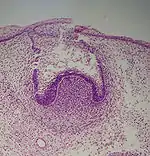

A: enamel organ

B: dental papilla

C: dental follicle

The tooth germ is an aggregation of cells that eventually forms a tooth.[2] These cells are derived from the ectoderm of the first pharyngeal arch and the ectomesenchyme of the neural crest.[1][3][4] The tooth germ is organized into three parts: the enamel organ, the dental papilla and the dental sac or follicle.